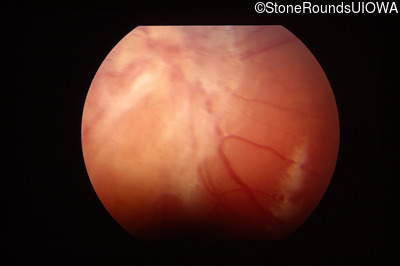

Fundus Photography - Right - Light Perception